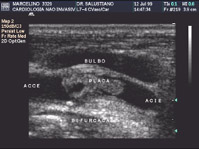

Duplex Scan de Carótidas e Vertebrais

Por ter uma posição anatômica mais superficial e pela tecnologia dos trandutores de alta frequência permitiu um reconhecimento anatômico e funcional desses vasos e do fluxo sanguíneo de forma bem adequada. É possível localizar com precisão o local das placas de ateroma, bem como detalhes de superfície dessas placas e até mesmo visibilizar ulcerações que aumentam o risco de embolização cerebral que a arteriografia não identifica.

O Duplex Scan tornou-se o método não invasivo de eleição para a avaliação dessas artérias e, em casos especiais, o tratamento cirúgico está sendo realizado prescedido da arteriografia.